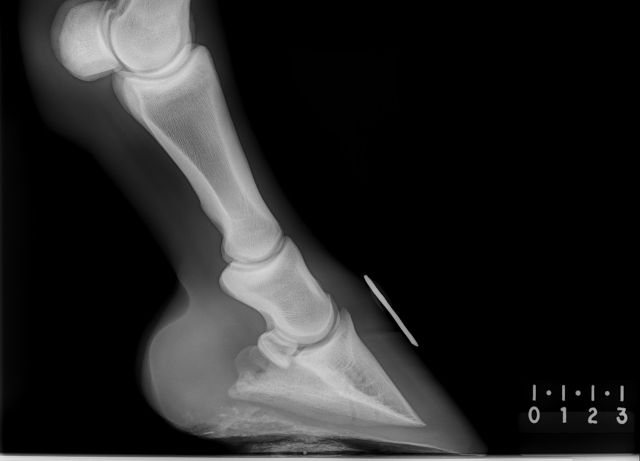

The solution is simple: mobile digital radiography. We have recently upgraded our old Cuattro Slate DR system to the new state of the art Cuattro Slate 6 digital system. This allows us to perform hospital quality X-rays on site with ease – we are currently the only equine practice in the area to be able to offer this service of this quality!

Due to the wireless system it makes taking x-rays much more efficient and hassle free. There is no need to travel your horse to a hospital so therefore makes it much more cost effective process and reduces the potential stress to you and your horse. This system also assists in achieving a much more rapid diagnosis.

Unlike the old-fashioned plate and film systems, the new Cuattro Slate connects wirelessly to a touchscreen notepad. The images are captured immediately and can be assessed and adjusted within seconds. All images taken are of the highest resolution and can be examined on site from the notepad.